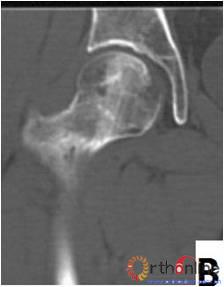

2. 依据SARS后ARCO分期Ⅰ期的ONFH患者(自然进展组)初次普查时的MRI或CT片,选用冠状位正中层面的T1WI(MRI)图像或冠状位二维重建的正中层面的(CT)图像,根据坏死灶占据外侧柱情况分为三型。Ⅰ型:坏死灶占据中央及内侧柱,外侧柱完全保留;Ⅱ型:部分外侧柱被坏死灶占据,部分保留(至少外侧皮质保留);Ⅲ型:坏死带穿透股骨头骨髓与外侧皮质,外侧柱无存留。(图2)

图2-1

图2-2

图2-3

图2 依据股骨头外侧柱存留情况,股骨头坏死的分型。(图2-1)分为Ⅰ型(外侧柱全部存留)(A)MRI图像显示;(B)7年后CT显示股骨头仍未塌陷;(图2-2)Ⅱ型(外侧柱部分保留)(A)MRI显示外侧皮质存留;(B)4年后CT显示股骨头仍未塌陷;(图2-3)Ⅲ型(坏死带穿透股骨头);(A)MRI显示坏死带;(B)2年后股骨头塌陷

Fig 2 According to preservation of the lateral pillar, the necrosis was divided into three types. (Fig 2-1)Type Ⅰ: Whole lateral pillar preserved (A) MRI showing; (B) no collapse occurred seven years later by CT showing. (Fig 2-2)Type Ⅱ: Preservation of the partial lateral pillar, (A) MRI showed the preservation of the lateral cortical bone; (B) no collapse of the femoral head four years by CT. (Fig 2-3)Type Ⅲ: the necrotic line pass through the cortical bone and bone morrow ;(A) MRI showed the necrotic line; (B) collapse of the femoral head occurred two year later.